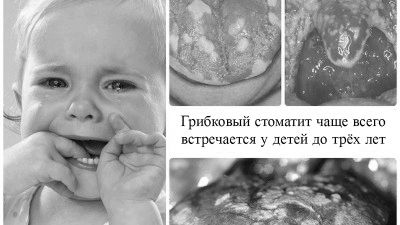

- Стати причиною розвитку захворювання може такий грибок, як кандида. Він вражає слизову порожнини рота малюка і супроводжується цей процес появою білого нальоту. У народі таке захворювання отримало назву «молочниця» і найчастіше воно діагностується у дітей у віці до року, а ось малюки після трьох років з такою патологією стикаються досить рідко.

кандидозний стоматит

Лікування цього виду стоматиту, перш за все, спрямована на створення лужного середовища в порожнині рота дітей, оскільки підвищена кислотність робить позитивний вплив на перебіг запального процесу, а також є ідеальним місцем для розмноження грибків і бактерій. У домашніх умовах у дітей трьох років лікування кандидозного стоматиту можна проводити наступними способами: